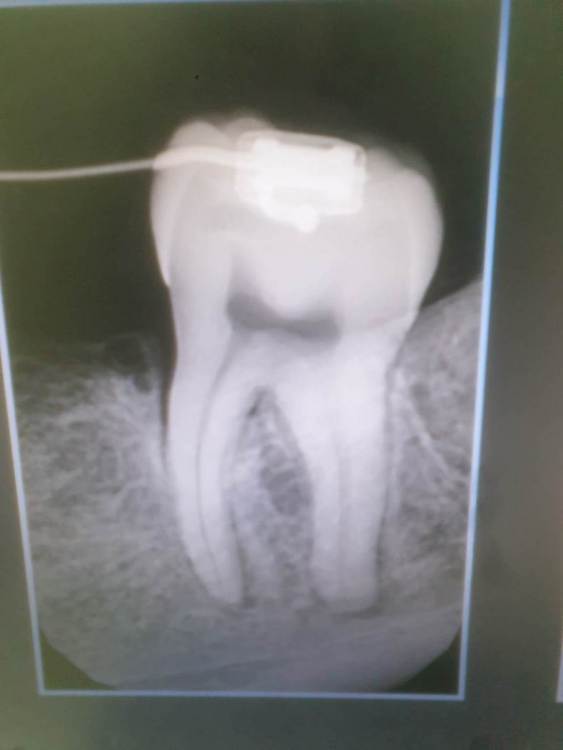

Elffa Опубликовано 28 октября, 2023 Автор Поделиться Опубликовано 28 октября, 2023 Пациентка 20 лет. Проходит ортодонтическое лечение в нашей клинике. Обратилась с жалобами на боль 3.7 Болел около недели. Реакция на холод + перкуссия + переходная немного болезненна. Зуб раннее не лечен. Вскрыла, пульпа витальна. Кальций на 2 недели, далее постоянная пломбировка. Пациентка требует выписку. Как грамотно описать диагноз? Апикальный периодонтит? Ссылка на комментарий

Elffa Опубликовано 28 октября, 2023 Автор Поделиться Опубликовано 28 октября, 2023 2 часа назад, АнтонТЛТ сказал: Откуда там периодонтит, если зуб витальный. т к рентгенпризнаки периодонтита. Но и зуб "живой".... 1 час назад, Irouil сказал: Травматического генеза?) А что с пародонтом при осмотре? Пульпит других зубов исключён? Да, думаю травматического. Пародонт....подвижности нет, карман с медиальной стороны. Зуб наклонен язычно сильно. Ретроградный периодонтит может быть? Или все-таки пульпит хронический написать???? Ссылка на комментарий

АнтонТЛТ Опубликовано 28 октября, 2023 Поделиться Опубликовано 28 октября, 2023 Это не рентген признаки периодонтита, это рентген признаки апрайтинга зуба (изменения наклона зуба при ортодонтическом лечении) 2 1 Ссылка на комментарий

Бардо Опубликовано 11 ноября, 2023 Поделиться Опубликовано 11 ноября, 2023 если термопроба норма, то резать такой зуб было несколько преждевременно, как мне кажется. Вся симптоматика и рентген - результат ортодонтии, к гадалке не ходи Ссылка на комментарий